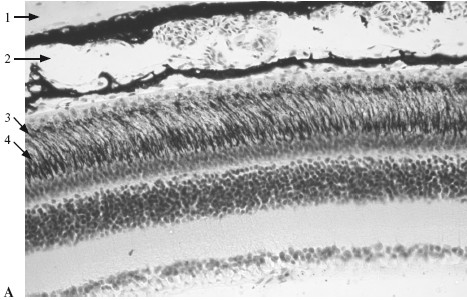

10.1.2. Рецепторный аппаратСетчатка (retina) – внутренняя оболочка глазного яблока, воспринимающая световые раздражения и превращающая их в нервный сигнал. Состоит из двух листков: светочувствительного, содержащего фоторецепторные нейросенсорные клетки с их отростками – палочками и колбочками, и наружного – пигментного (рис. 10.1).

Рис. 10.1. Сетчатка на свету (А) и в темноте (Б). х 130.

1 – склера; 2 – сосудистая оболочка; 3 – пигментный эпителий сетчатки; 4 – слой палочек и колбочек с отростками пигментных клеток, заполненных пигментом; 5 – слой палочек и колбочек с отростками пигментных клеток, свободных от пигмента; 6 – наружный зернистый слой.

Пигментный эпителий – самый наружный слой сетчатки. Он состоит из призматических полигональных клеток, расположенных на базальной мембране. Наружная часть клеток содержит ядра. От внутренней поверхности клеток отходит 8—10 отростков, заполненных меланином. Пигментированные отростки отделяют фоторецепторы друг от друга. На свету пигмент переходит из тела клетки в ее отростки, препятствуя рассеиванию света между соседними фоторецепторами. В темноте пигмент перемещается в ядросодержащую часть тела клетки.